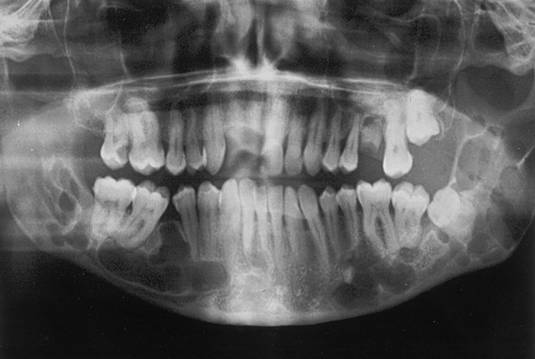

Fig.13 Ortopantomografia unui pacient cu sindrom Gorlin, ce prezinta multiple radiotransparente mandibulare, corespunzatoare keratochisturilor.